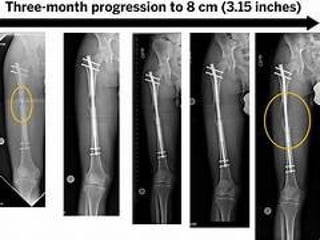

 Short stature → GH therapy, extended limb

lengthening (complications are frequent)

Treatments and Managements Basedon clinical manifestations  Short stature → GH therapy, extended limb lengthening (complications are frequent)  Kyphosis → bracing support to prevent persistence of thoracolumbar kyphosis  Hydrocephalus → know the symptomps of increased ICP → ventriculoperitoneal shunting